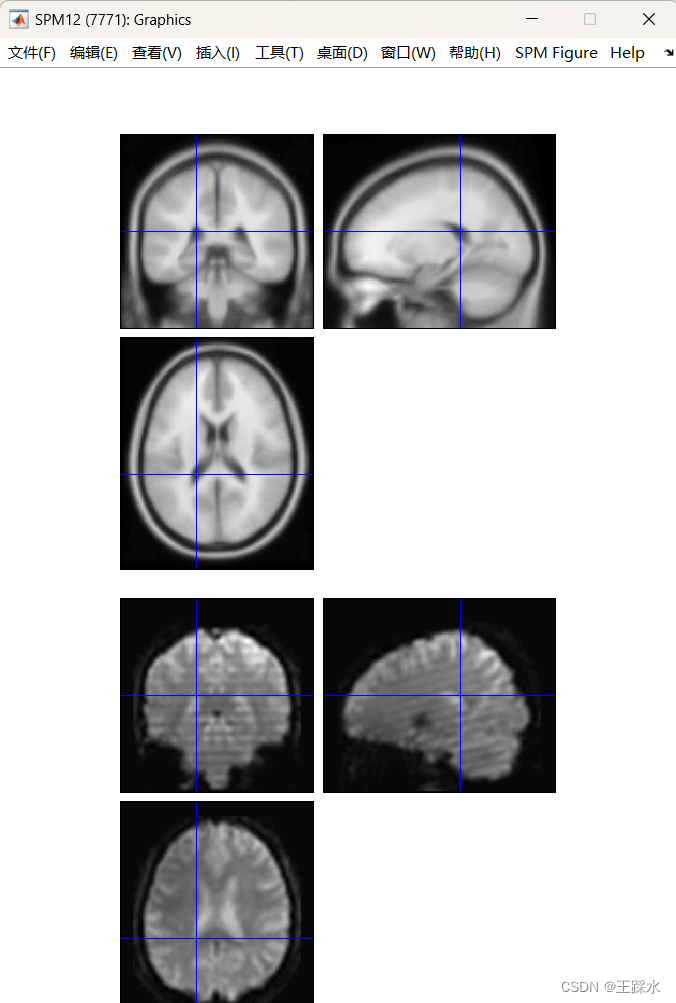

3、空间配准

这部分就是要把大头、小头都配准到一个标准的头中!我用的是:功能像向结构像看齐、结构像向标准空间看齐。

coregister 是功能像配准到结构像(选择estimate就可以,只需要输出那个数值,不需要生成新的图像);normalise 是结构像配准到标准空间。

空间配准完成!展示的是一个标准空间还有一个是功能像生成的第一帧